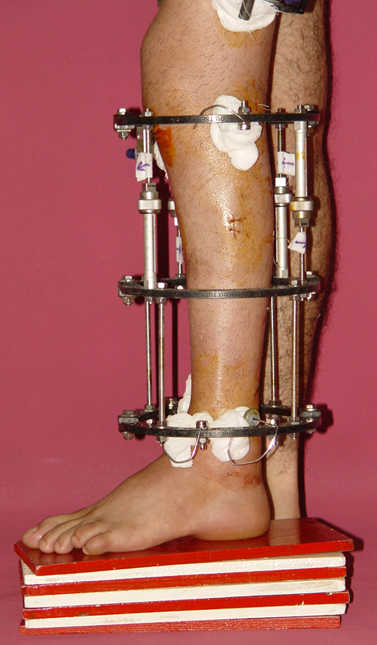

3. POSTTRAUMATIC LOWER LIMB SHORTNESS (MALUNION)

This type of shortness occurs after a fracture heals in a shortened position. Most cases are seen in adults and can be treated with one lengthening operation. Additional deformities can be corrected simultaneously. Most of these cases can be treated with lengthening over nail or just corrections and intramedullary nailing.